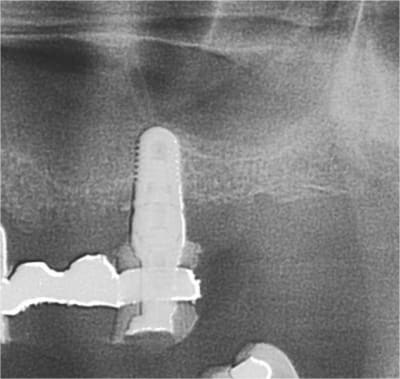

Pose d’un implant au maxillaire dans une zone de faible densité

Léger summers

je connais cette radio!!!!!...;-))

P.S: tout va bien, prothèse d'usage prévue fin septembre...;-))